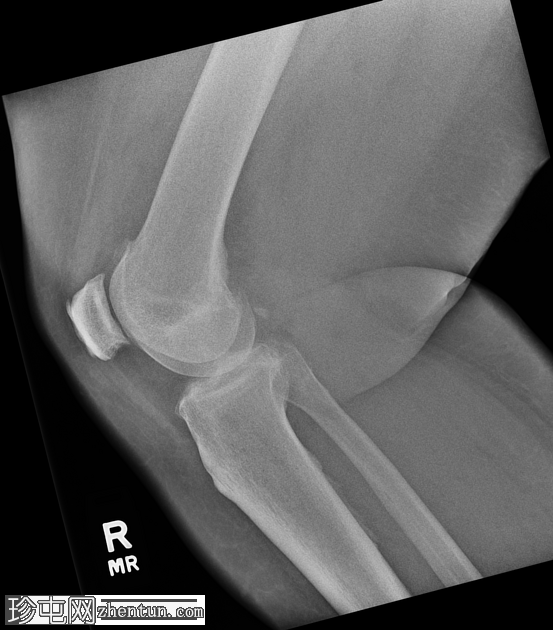

斜位片

侧位片

右膝中度骨关节炎(3级),表现为内侧胫股关节和髌股关节间隙狭窄,边缘可见骨赘、髌骨骨刺和胫骨棘突。

内侧副韧带近端附着处股骨内侧髁附近可见长圆形软组织骨化,提示为佩莱格里尼-斯蒂达(Pellegrini-Stieda)损伤。